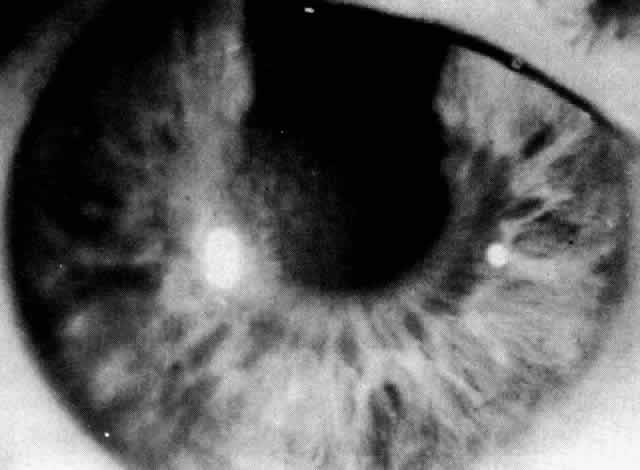

Patients with Fuchs' dystrophy rarely present with symptoms until after 50 years of age. Patients progress through three phases. In phase one, patients are asymptomatic and simply have guttata (Fig. 11) and pigment dusting of the endothelium. Patients who progress to phase two present with complaints of hazy vision and glare as stromal and epithelial edema develop. Epithelial edema progresses to bullae that may rupture and may cause severe pain. In phase three, subepithelial connective tissue develops and edema decreases. Patients become more comfortable but have a significant decrease in vision.

Fig. 11. Fuchs' dystrophy: beaten metal appearance of endothelium.

Guttata are not specific for Fuchs' dystrophy. They are products of abnormal endothelial cells can be present with inflammation, trauma, or aging. Up to 70% of the population over the age of 40 may have guttata.183